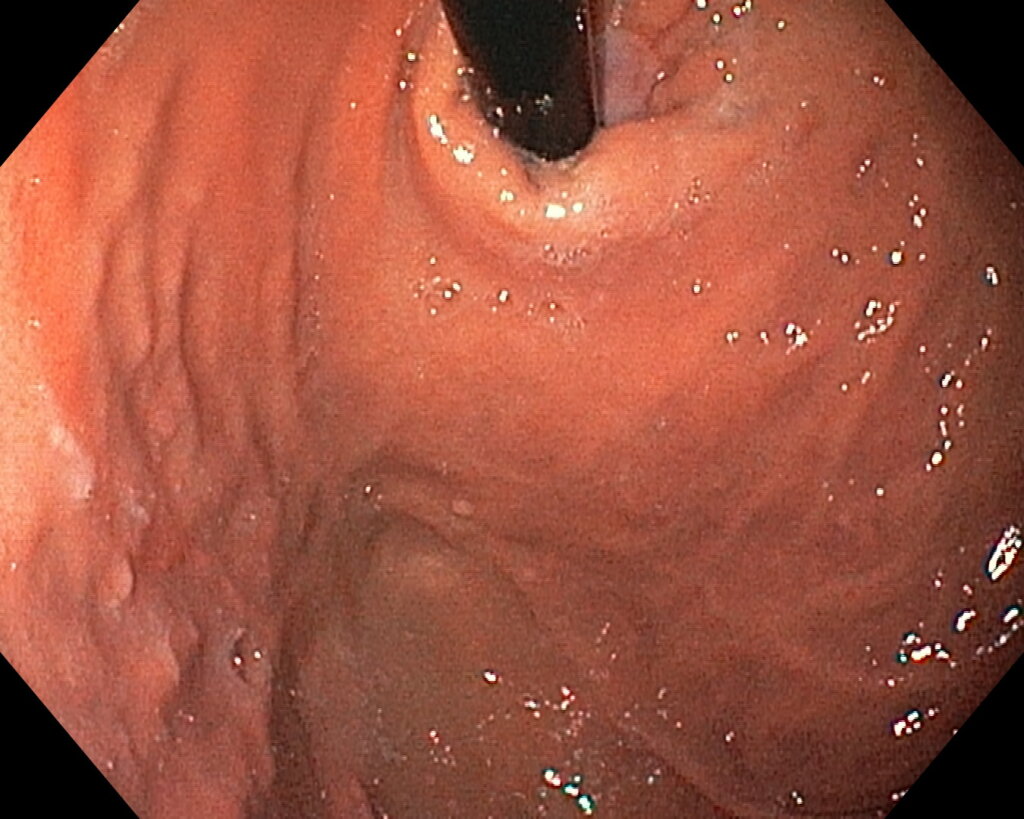

После предварительного обследования произведена операция: ESG + АПК (APC) свода; всего использовано 6 швов, время процедуры ≈ 120 минут.

Под видеоконтролем выполнена эндоскопическая рукавная гастропластика: сшивание стенок желудка при помощи аппарата Overstitch Boston Scientific по длине тела с целью уменьшения объёмов съедаемой пищи.